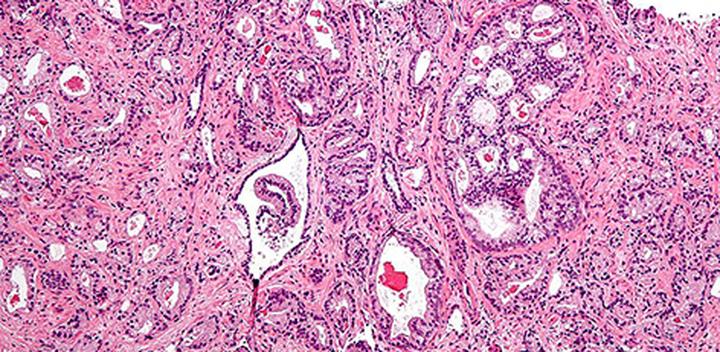

Badanie histopatologiczne jest kluczowym narzędziem diagnostycznym. Polega na mikroskopowej analizie fragmentów tkanek, co pozwala na ocenę ich struktury oraz identyfikację ewentualnych patologii. W kontekście poronienia materiał do analizy najczęściej pochodzi z łyżeczkowania jamy macicy, podczas którego usuwane są pozostałe tkanki płodowe. Dokładność badania może pomóc zrozumieć, co wydarzyło się podczas ciąży oraz wskazać czynniki wymagające dalszej interwencji medycznej.

Wyniki badania histopatologicznego mają istotne znaczenie. Mogą wykazywać obecność schorzeń, takich jak ciążowa choroba trofoblastyczna. Mogą one zagrażać zdrowiu kobiety. Gdy analiza wykazuje brak komórek płodu lub łożyska, może to prowadzić do podejrzenia ciąży ektopowej, co wymaga pilnej interwencji medycznej.

Badanie histopatologiczne polega na mikroskopowej ocenie fragmentów tkanek. Dzięki temu można zdiagnozować ewentualne nieprawidłowości, takie jak choroby trofoblastyczne czy ciąża ektopowa, co pozwala ustalić, czy istnieją jakiekolwiek stany zagrażające zdrowiu matki.

Badanie histopatologiczne jest kluczowym narzędziem diagnostycznym, które pozwala na mikroskopową analizę fragmentów tkanek, co umożliwia ocenę ich struktury oraz identyfikację ewentualnych patologii, które mogą wyjaśnić przyczyny poronienia.

Zły wynik badania histopatologicznego może wykazywać obecność schorzeń takich jak ciążowa choroba trofoblastyczna lub wskazywać na brak komórek płodu, co może sugerować ciąże ektopową, a te stany wymagają pilnej interwencji medycznej.